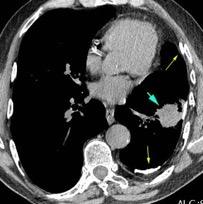

Tromboembolismo pulmonar.

Frecuencia del derrame:

Rx: 32%. TC: 47%

Unilateral. 85%

< 1/3 del hemitórax: 90%

Todos exudados

58% con eritrocitos

21% tabicación lo que causa demora en el diagnóstico

TEP. Empiema pleural. Atelectasia redonda

Porcel JM et al. Analysis of pleural effusions in acute pulmonary embolism: radiological and pleural fluid data from 230 patients. Respirology 2007/ Iguchi T et al. Desquamation of the subpleural lung parenchyma caused by empyema after pulmonary embolism: A case report. Respirol Case Rep. 2022 .